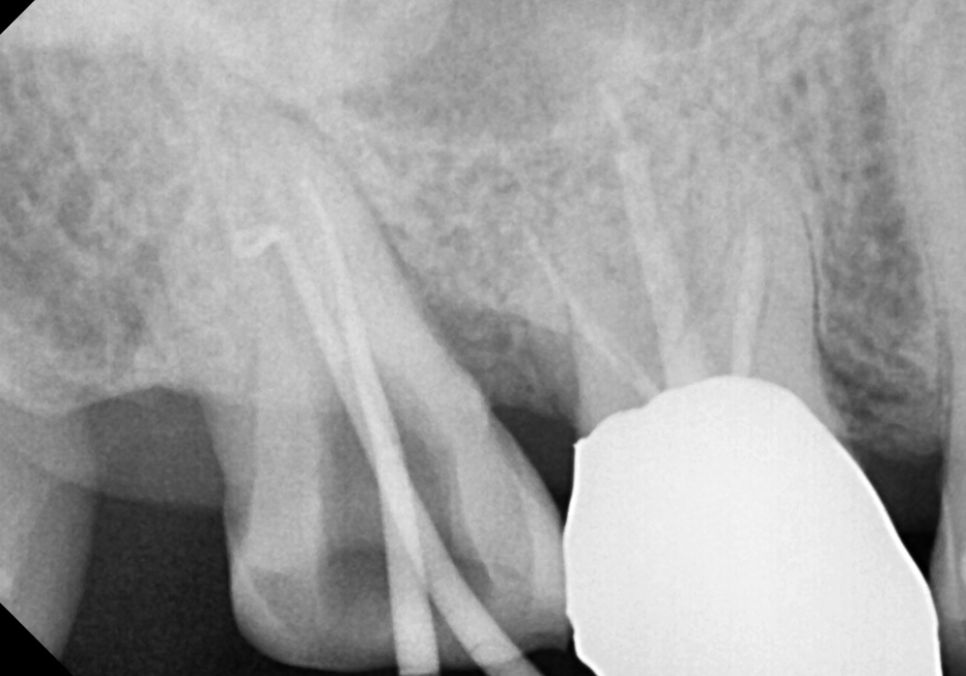

231221

겉으로 보기에는 큰 충치가 없어 보였지만,

자세히 살펴보니 씹는 면을

가로지르는 미세한 실금이 관찰되었습니다.

240213

방사선 사진상으로는 다행히 금이

뿌리까지 완전히 내려가지는 않은 것으로 보여서,

환자분과 상의 끝에 자연치아를 살려보기 위한

신경치료를 시작했습니다.